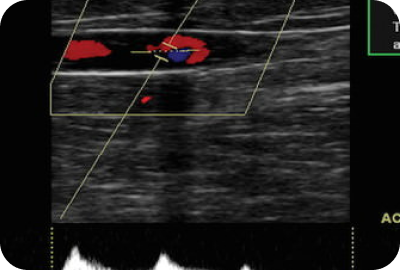

A pulse-doppler morphologic evaluation is used to evaluate blood flow through the major veins of both lower extremities. This test is used to find blocked or narrowed blood vessels and blood clots, which if left undetected can break off and travel through the bloodstream to the hearts or lungs.